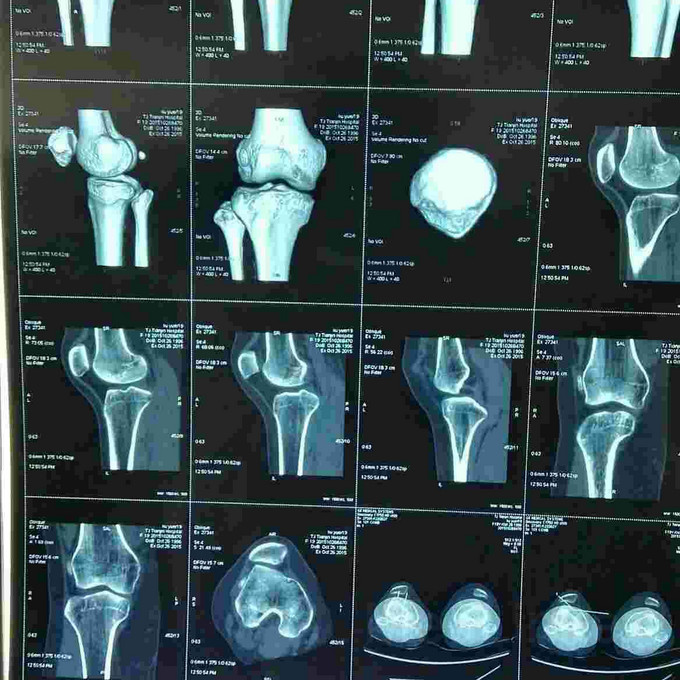

患者女,19岁,双膝关节习惯性髌骨脱位10余年,多家医院建议手术治疗,2个月前摔伤致左髌骨脱位,于某院行手术治疗,经家人商讨后决定再行右膝手术治疗来我院。请老师们指点是否需要调整髌骨远端力线?做何手术最为简单有效?具体是做单纯外侧支持带松解?外侧支持带松解+内侧关节囊缩紧筋膜成形?外侧支持带松解+髌腱手术?外侧支持带松解+胫骨结节内移?还是外侧松解+内侧紧缩成形+胫骨结节内移?还是什么?